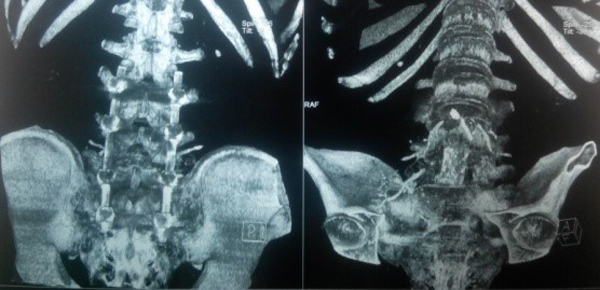

Trên X-quang, CT scanner khối u phá hủy vỏ xương gần hết thân và cuống sống L5.

Bệnh nhân được phẫu thuật ngày 29/9/2015 với 2 đường mổ phía sau và phía trước. Với đường mổ phía sau, bệnh nhân nằm sấp, cố định nẹp vít các đốt L3L4S1-xương cánh chậu, sau khi bắt vít chúng tôi tiến hành cắt bỏ cung sau ngang cuống L5 để giải ép thần kinh, lấy bỏ phần u phá hủy cuống L5 hai bên, đặt rod, ốc khóa trong cố định và đặt 1 dẫn lưu. Kết quả sinh thiết tức thì: u TBKL độ 2. Thời gian phẫu thuật đường sau: 2 giờ 30 phút.

Do khối u nằm ngay sau ngã ba chủ chậu nên chúng tôi đã phải bộc lộ tỉ mỉ để bóc tách u khỏi động mạch, tĩnh mạch và niệu quản. Khối u to nên chúng tôi phải lấy bớt một phần u để tiếp tục bóc tách tránh phải cắt mạch để bộc lộ. Sau khi lấy bỏ phần u xâm lấn ra trước, tiến hành cắt thân L5, đặt lồng titan có xương mác đồng loại và bột xương để ghép thay thế. Đặt một dẫn lưu sau phúc mạc và một dẫn lưu Douglas trước khi đóng bụng. Thời gian đường mổ phía trước 3 giờ 30 phút, tổng thời gian mổ 6 giờ.

Ngoài mục tiêu cắt bỏ rộng rãi khối u, việc bảo tồn chức năng thần kinh và tái tạo lại giải phẫu để đạt được sự ổn định trục và chức năng cơ học của cột sống là điều hết sức quan trọng [14]. Sau khi lấy toàn bộ thân L5, chúng tôi đặt lồng titan có xương mác đồng loại bên trong làm cầu xương thay thế, đảm bảo trục cũng như độ ưỡn cột sống.